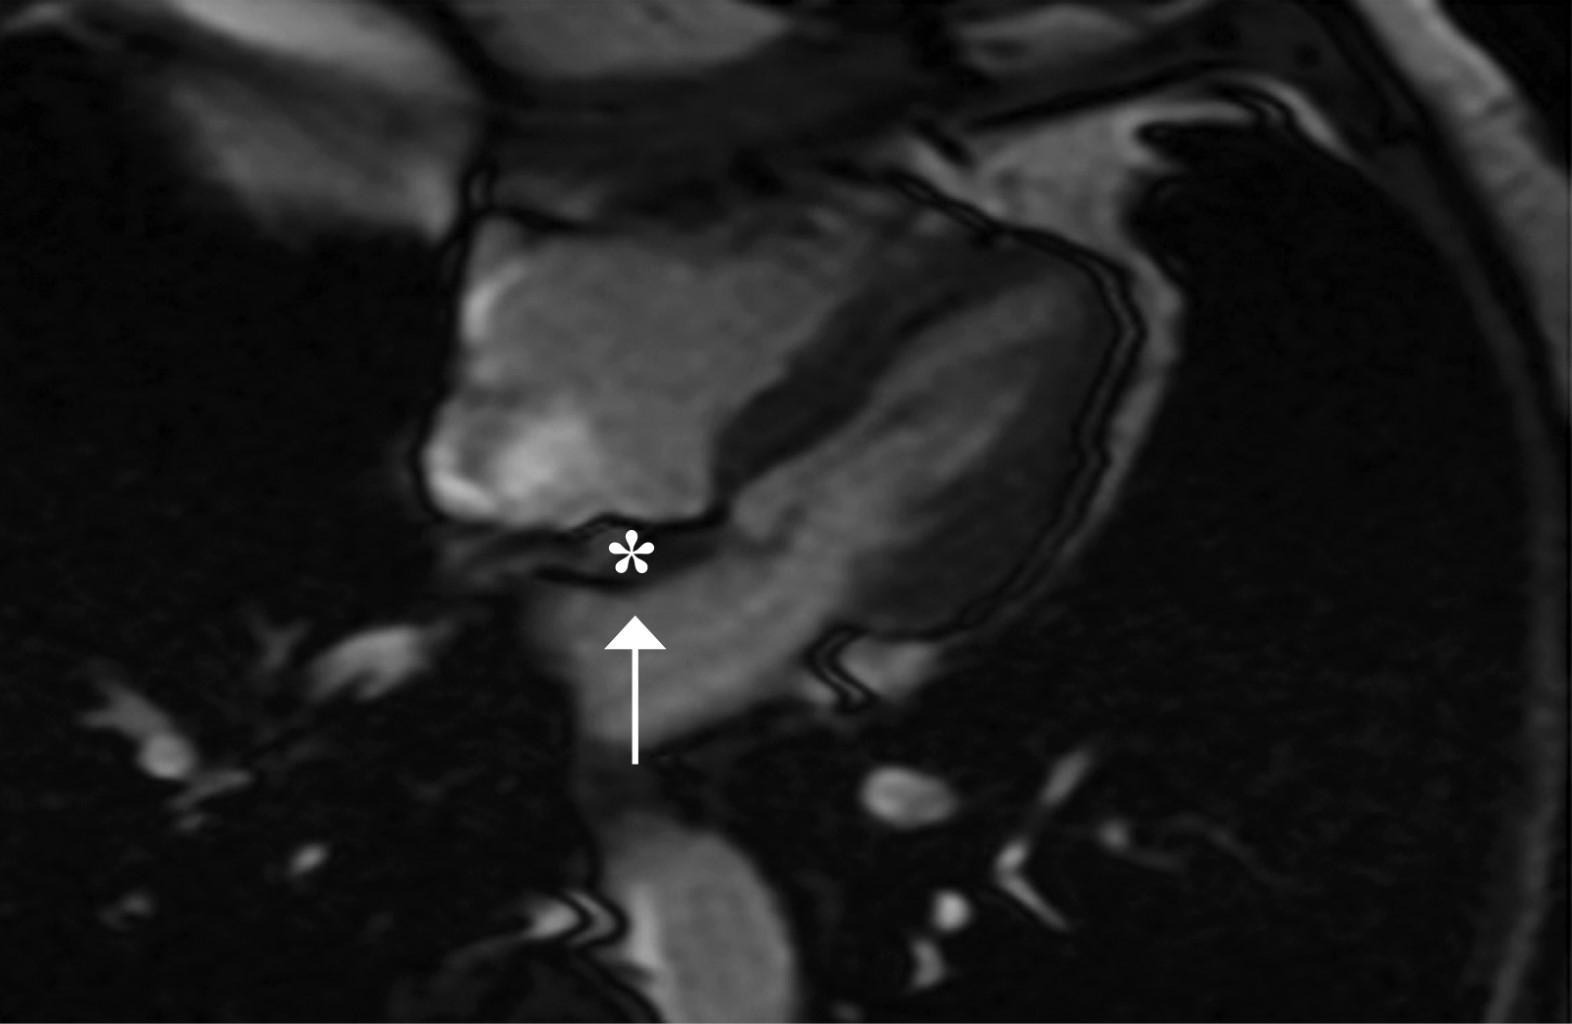

Palpitaciones como manifestación de hiperplasia lipomatosa del tabique interauricular: reporte de caso y revisión de literatura

La hipertrofia lipomatosa del tabique interauricular se reconoce cada vez más y debe considerarse como parte del diagnóstico diferencial de uier tumor cardiaco. Presentamos el caso de un paciente de 70 años que acudió al servicio ambulatorio por palpitaciones. El ecocardiograma transtorácico (ETT) detectó engrosamiento del septo interauricular de predominio proximal con respecto de la fosa ovalis. El diagnóstico fue confirmado por resonancia magnética cardiaca. En tales casos, la opinión de un cardiólogo experto en imagen cardiaca ayudaría a evitar un diagnóstico erróneo y una intervención innecesaria. Esta condición es más común de lo que se pensó inicialmente y sigue siendo poco reconocida por la mayoría de los médicos.

Figura 3